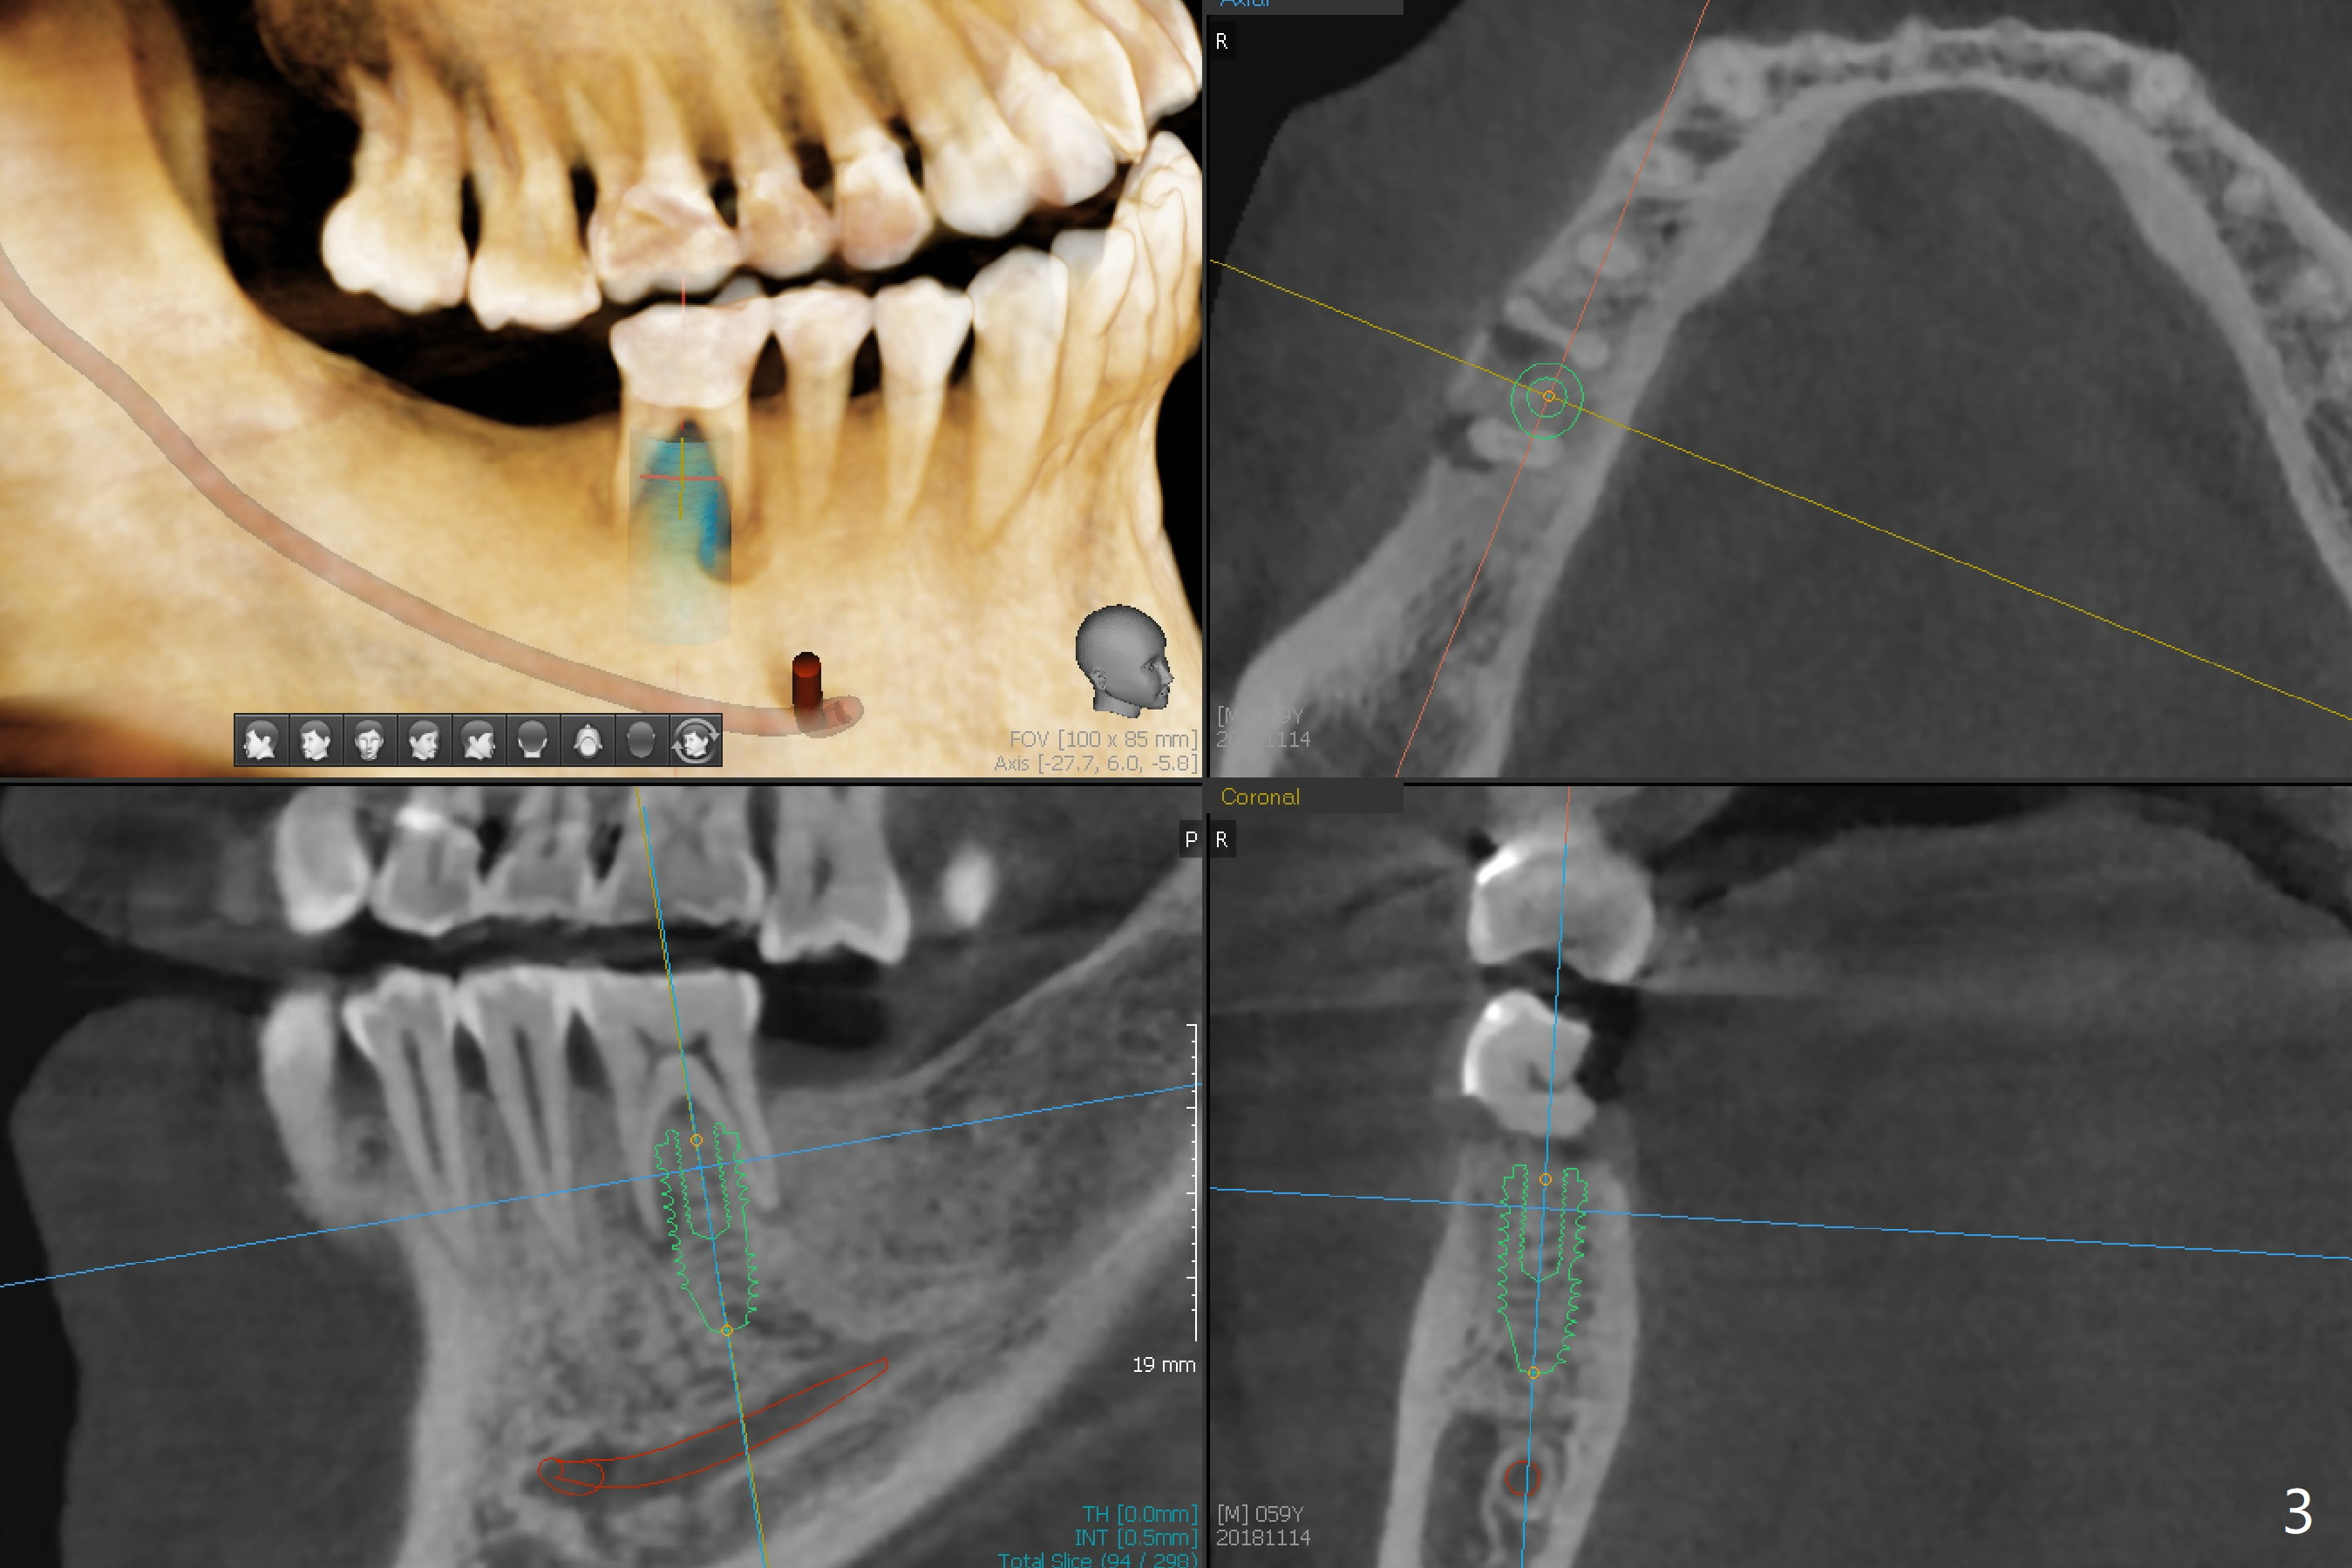

A 59-year-old man has subgingival fracture of the lingual cusps of the tooth #30 (Fig.1) with PARL, especially of the mesial root (Fig.2). An immediate implant will be placed slightly distolingually (Fig.3), while the delayed implant at #31 will be placed in a restorative position (Fig.4). Treat plan orthodontic intrusion of the tooth #2 if the latter is salvageable with periodontal lesion (Fig.1). Keep the tooth #1 in case bands and segmental wire are needed. It will be extracted prior to impression. After extraction, place a bony anchor pin at #31 for #30 osteotomy. When an implant is placed at #30, place a fixture anchor pin and finish osteotomy at #31.